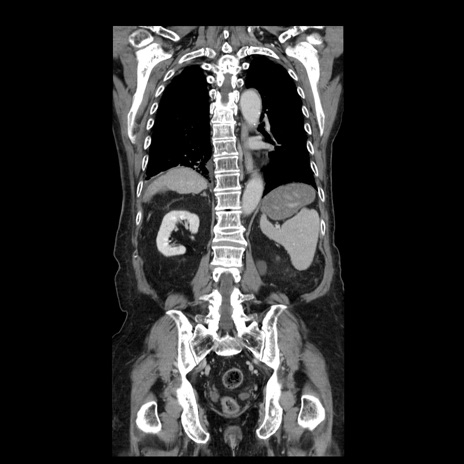

症例21(冠状断像)

【症例】70歳代男性

【主訴】腹痛

【現病歴】肝硬変・肝細胞癌にてかかりつけの方。約9時間前に食後より腹痛出現。症状が徐々に増悪し、嘔吐出現したため来院。

【既往歴】肝硬変、肝細胞癌(RFA、TACE後)

【身体所見】意識清明、表情苦悶様、BT 36℃、BP 129/78mmHg、P 88bpm、SpO2 97%(RA)、右上腹部から心窩部にかけて圧痛あり、反跳痛なし、筋性防御あり。

【データ】WBC 5800、CRP 0.16